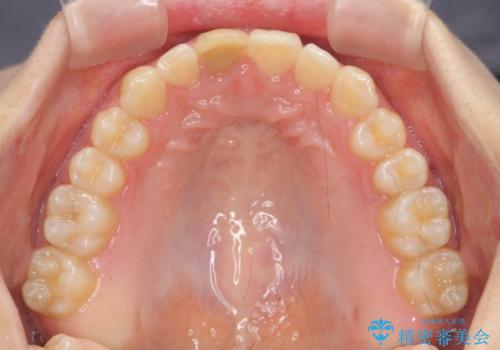

前歯のがたつき 深い噛み合わせを改善したい

- 「前歯のガタつきをきれいにしたい、噛んだ時に下の前歯が見えないことを改善したい」とマウスピース矯正を希望され来院されました。

マウスピースに加え、矯正用マイクロインプラントやゴムを併用し、がたつきや噛み合わせの深さを改善していきます。

ゴムかけやマウスピースの装用時間、しっかりとマウスピースをはめ込むチューウィーをしっかりと使用したことで良好な治療結果を得ることができました。